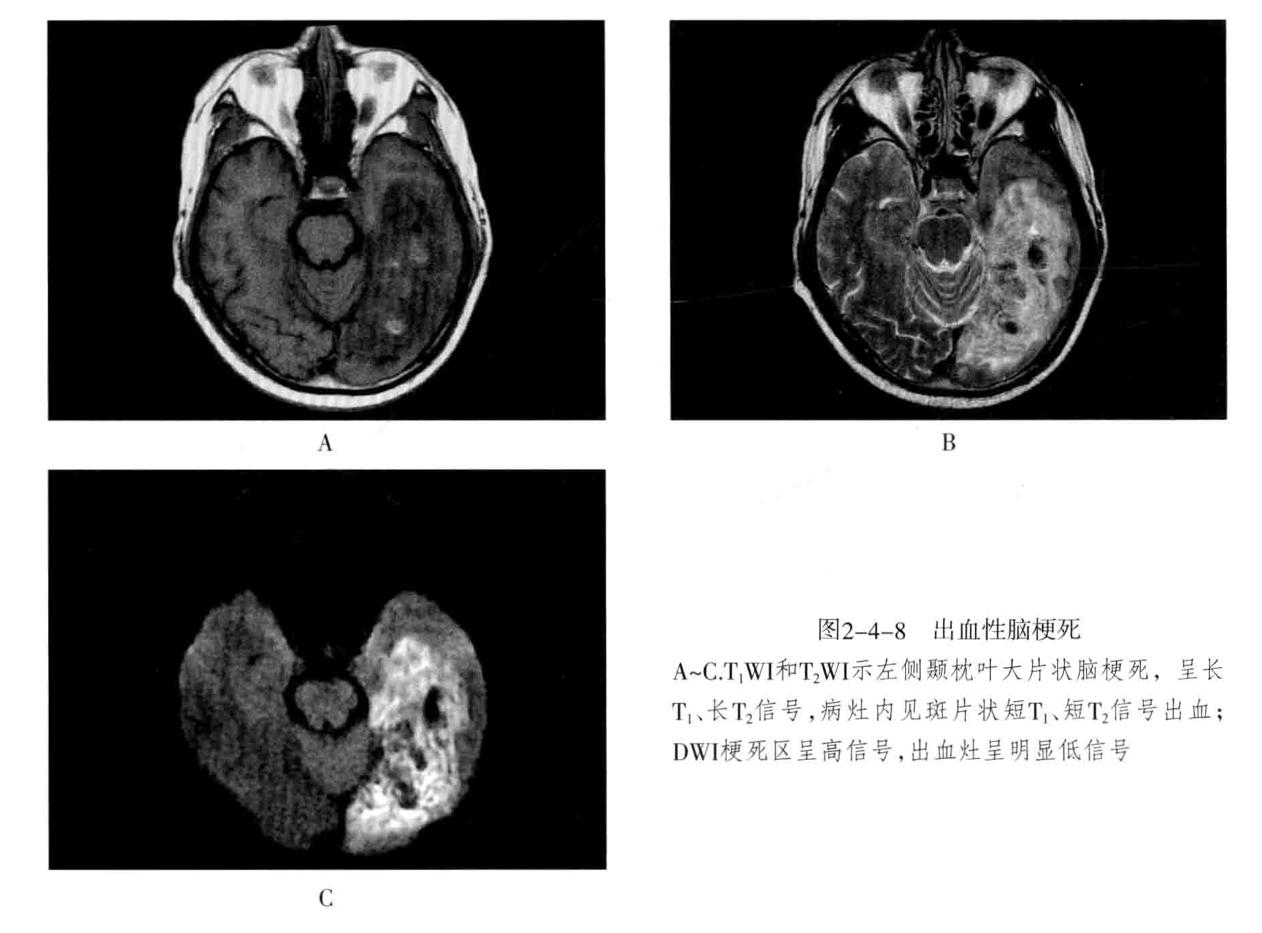

八、脑梗死:是一种缺血性脑血管疾病,常见有动脉闭塞性梗死和腔隙性脑梗死。主要病因为脑的大或中等管径的动脉发生粥样硬化,继发血栓形成,导致管腔狭窄、闭塞。以大脑中动脉闭塞最常见。脑梗死发生4-6小时脑组织发生缺血与水肿,继而脑组织出现坏死。1-2周后脑组织水肿逐渐减轻,坏死脑组织液化,梗死区出现吞噬细胞浸润,清除坏死组织,同时有胶质细胞增生和肉芽组织形成,8-10周后形成含液体的囊腔即软化灶。少数缺血性脑梗死在发病24-48小时后可因再灌注而发生梗死区内出血,转为出血性脑梗死。常见症状为偏瘫和偏侧感觉障碍、偏盲、失语等。

1. CT表现为脑组织内低密度灶,梗死后2-15天为脑水肿高峰期,此时可有脑水肿表现;梗死1个月以后,相邻部位的脑室、脑池或脑沟扩大,出现脑萎缩表现。增强后梗死区可出现不均匀强化,呈脑回状、条状、环状或结节状强化。梗死区强化是由于血脑屏障破坏、新生毛细血管和血液灌注过度所致。

2. MRI在脑梗死6小时之内,由于细胞毒性水肿,DWI可发现高信号,此后发生血管源性水肿、细胞死亡、髓鞘脱失、血脑屏障破坏,T1与T2弛豫时间延长。梗死后期,小的病灶不显示,表现为脑萎缩,大的病灶表现为软化灶。